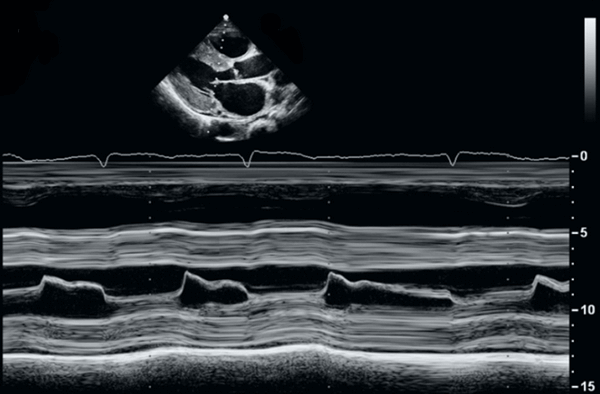

М-режим эхокардиографии является полезным в документировании асимметричного утолщения межжелудочковой перегородки, передне-систолического движения передней створки митрального клапана, и среднесистолического прикрытия аортального клапана. Непропорциональная септальное утолщение миокарда проявляется также в ПЖ и нижней стенки миокарда. Передне-систолический ход створок митрального клапана можно увидеть и в прочих гипердинамических кардиальных условиях. Двумерная (2D) эхокардиография остается главным подходом выбора для установления диагноза гипертрофическая кардиомиопатия. Кроме того, подробная морфологическая характеристика обеспечивается 2D эхокардиографической визуализацией. Наиболее частой из морфологического разнообразия выявляется гипертрофическая кардиомиопатия, которая состоит из диффузного утолщения желудочков, перегородки и переднебоковой свободной стенки (70%-75% случаев). Гипертрофия, которая сопровождается утолщением базальной зоны межжелудочковой перегородки (10%-15% случаев), концентрическая гипертрофия (5% случаев), апикальная гипертрофия (

Размеры полостей ЛЖ и ПЖ обычно нормальные или незначительно увеличены, но наблюдается нарушение сократительной способности стенок желудочков, наблюдаемое в М-режиме и 2-мерной эхокардиографии. Возможна дилатация ЛП и ПП.

Нарушение диастолической функции ЛЖ и ПЖ. Лучше всего это можно оценить по доплеровскому исследовании на ЭхоКГ. Часто наблюдается характерный аномальный «ограничительный паттерн» потока МК с очень большой E-волной и небольшой A-волной.